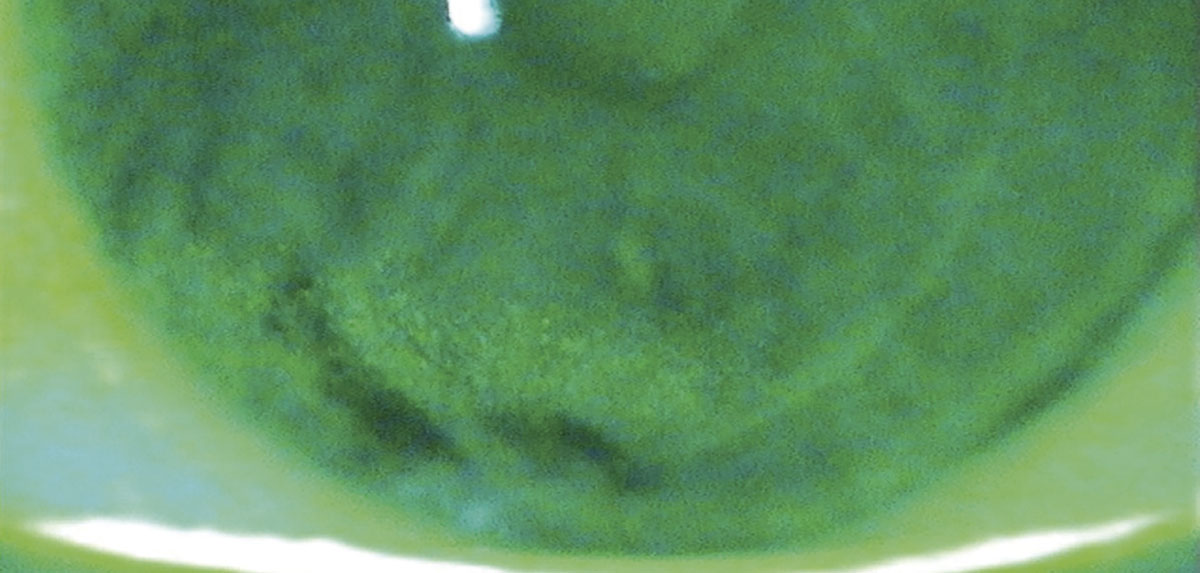

Figura 1. Queratopatía punteada inferior en un paciente con antecedente de LASIK durante las mediciones preoperatorias para cirugía de catarata.

Foto: Dr. John Sheppard.